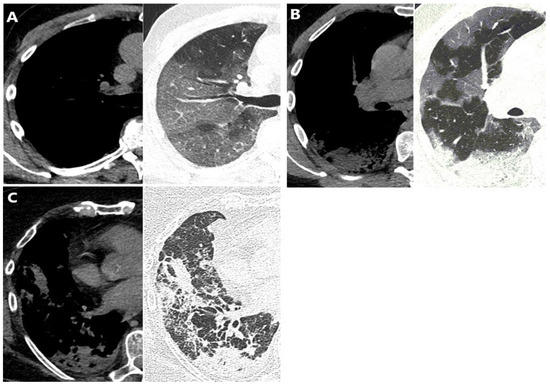

3.2. Pattern Distribution